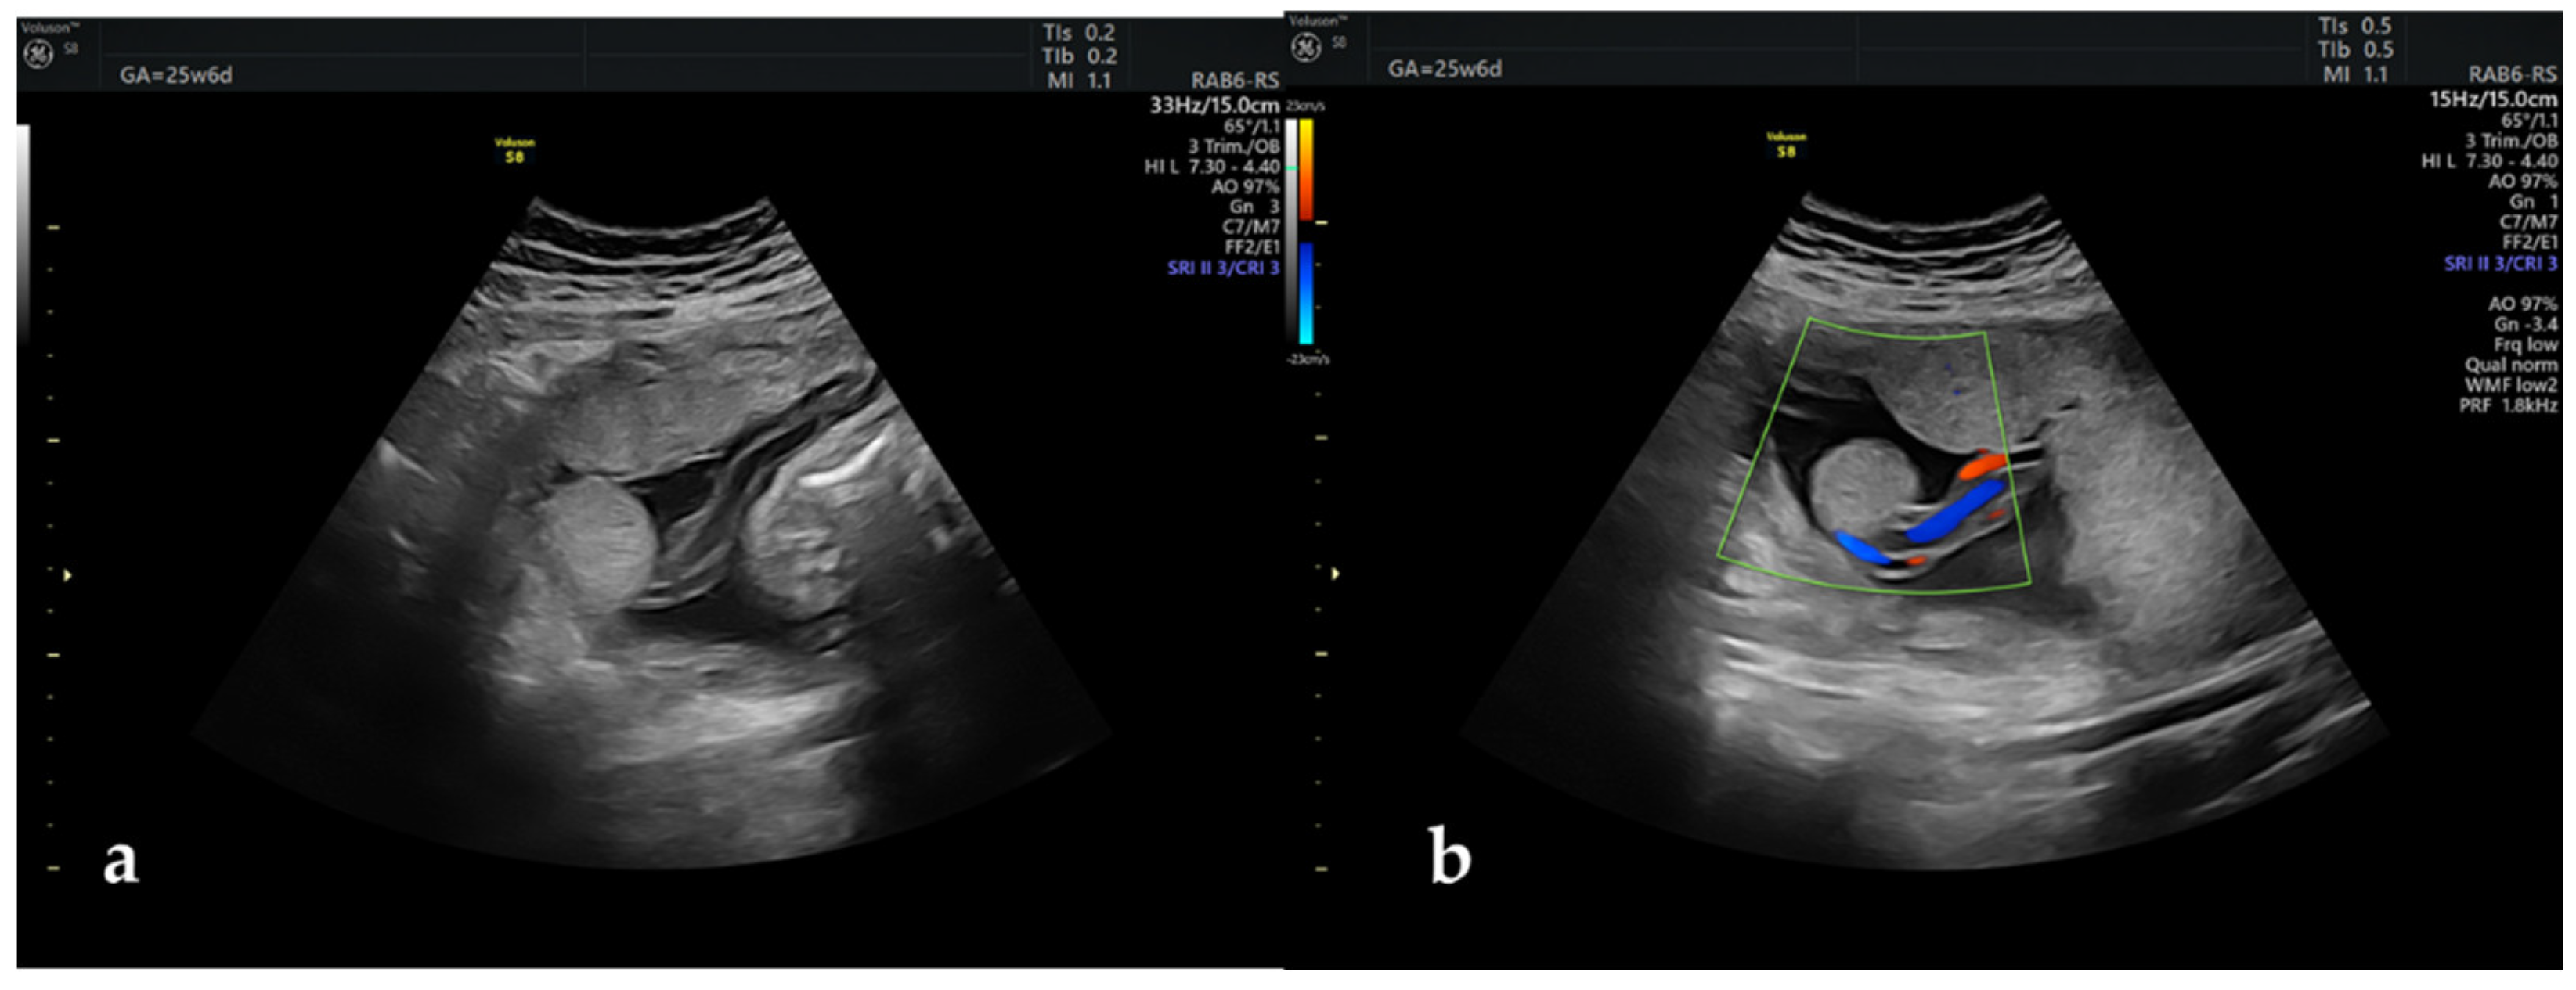

The repeat scan infirmed the VSD but raised the suspicion of an aberrant placental lobe located towards the left uterine flank, distant from the main placental mass (Figure 1). Doppler examination depicted the presence of umbilical vessels near the aberrant placental lobe, without being able to certify a vascularly connection with the main placental disk. No other placental abnormalities were identified during the ultrasound examination, the umbilical cord inserting centrally at the level of the main placental mass. Even though the location of the accessory lobe and supplying vessels were fundal, screening for vasa praevia was performed by vaginal ultrasound and this anomaly was excluded.

Figure 1. (a). Aberrant placental lobe b. (b). The contact with the umbilical vessels demonstrated by color Doppler flow.